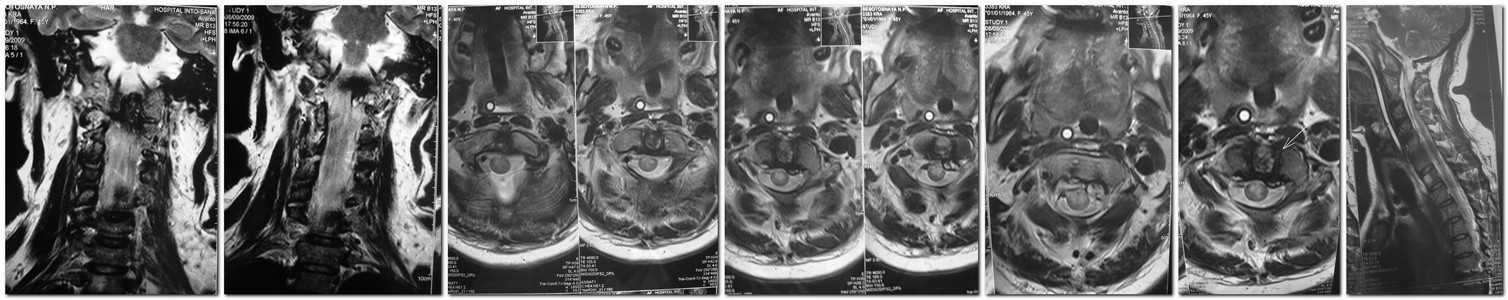

Тяжолый клинический случай...

Женщина 45 лет 12 дней назад ощутила повышения давления - потеря сознания. Доставлена в реанимационное отделения ЦРБ на Украине. Самостоятельно дихание и давление поддерживать не могла только на ИВЛ и вазопресорах.В сознании. Появилса тетрапарез. Переведина в обласное отделение реанимации. Конкретного диагноза нету. Через 7-8 дней тетрапарез постепенно начал исчезать, начала самостоятильно поддерживать давления но самостоятельное дыхание отсутствует.

Предполагаемый диагноз: Новообразование зубообразного отростка 2 шейного позвонка.

Сейчас на ИВЛ (установили трахеостому), прогресируют застойные явления лёгких.